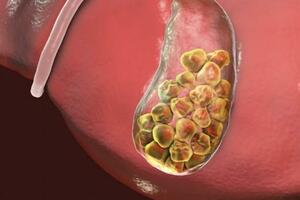

飛哥第一次犯病是因為左腳大腳趾戳了一下,沒在意(因為體檢從來沒注意過尿酸這一項,誰知哥尿酸早就很高了),現在尿酸開始玩兒命的往我腳趾上堆積,尿酸會變成結晶鹽尿酸石,就是像小鹽粒的石頭長在你的關節里、肌肉里、韌帶里,那酸爽,有人把疼痛分成十三級,女人生孩子是最痛的第十三級,痛風是第十二級,當你夜晚輾轉反側的時候,當你拖著一條殘腿上廁所的時候,真的是生無可戀,每次都想向天大吼:“我要截肢”,但是理智告訴你,截肢沒有用,你截不截肢,痛風就在那裡,大不了去你別的關節堆積,飛哥本人就是個活生生的例子,現在右腳、右膝關節、左腳踝、右手中指都被痛風攻陷了,這要是截肢飛哥剩下的東西可不多了。

扯遠了,那麼怎麼辦呢?最好的辦法是忌口,哥什麼都能忍,海鮮啤酒火鍋內臟豆製品,我忍,可是紅燒肉怎麼忍,告訴我怎麼忍,就這樣飛哥左腳大腳趾的關節就變成了這樣,哥想好了,等你長到長發及腰就去醫院做了你,不就一塊石頭嗎,終於在兩個月前哥的痛風再次發作,徹夜難眠,忍無可忍無需再忍,聯繫好一家三甲醫院申請住院,辦它。

穿鞋有點費勁

醫院不是你想住,想住就能住的,得排隊好不啦,還好碰到了一個很好的主治醫師(一個帥哥,叫張耀),幫我留意床位,也算順利。不過他們的副主任不好,老是嚇唬我,說尿酸高傷口不容易癒合,別人半個月,你可能一個月都好不了。最讓我受不了的是他說這痛風石不是一整塊石頭,是像一把石灰粉撒在麵糊糊里,到時候打開你的腳他們要反覆沖洗,而且絕對沖不幹凈,後面還會複發,如果壞死還有截肢的可能(天哪,哥把它養這麼大還想取出來收藏呢)。哼,哥是嚇大的嗎?我這麼疼,就想馬上截肢了會被你嚇到,再說了我舅舅家的表弟去年剛剛在唐山做完手術,聽說他的腳趾骨腐蝕的比較嚴重,從胯上取下一塊骨頭移植到了腳上,一共做了三次手術,就憑這,我也不能退縮了,接下來就是常規的住院環節了,每天上午輸液,輸降尿酸的碳酸氫鈉,吃的像和尚吃的一樣的東西,終於在入院第16天的時候尿酸從635降到了360,恭喜我,可以進手術室了。